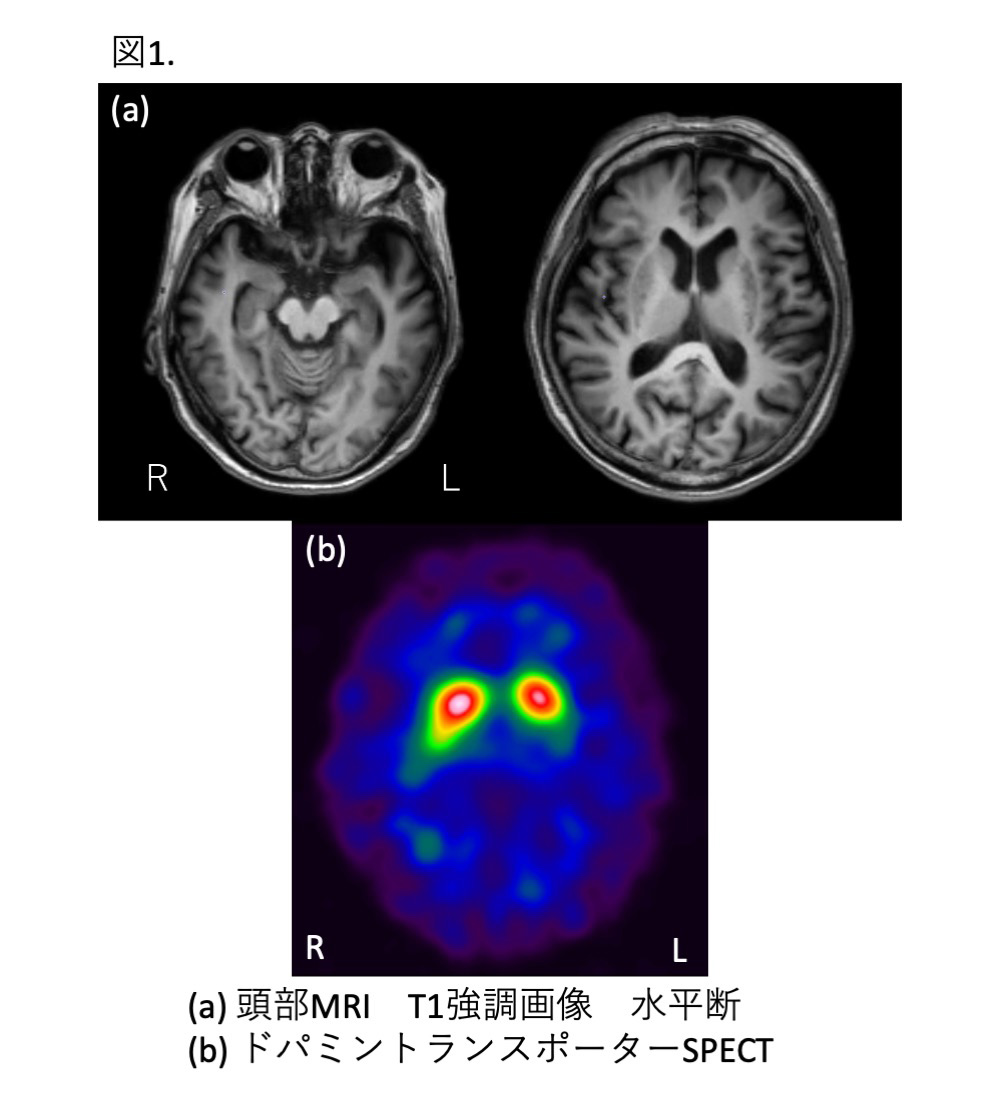

p.268掲載の図1